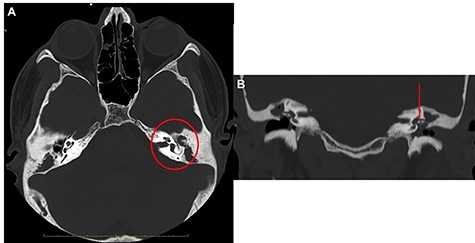

Head and neck contrast-enhanced computed tomography (CT) scan confirmed the presence of the fluid below the left sternocleidomastoid muscle (Fig. 2C–E) with massive opacification of the mastoid cells and the middle ear (Fig. 3A). Inflammatory tissue was identified in the middle ear with erosion of the ossicular bone chain (Fig. 3B). A diagnosis of CCOM with BA was made.

Ear CT scan; (A) axial view; the red circle shows the middle ear filled with inflammatory tissue, with erosion of the ossicular chain; (B) coronal view (the red arrow shows the erosion of malleus and incus); the malleus is not lateralized.